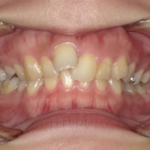

10代男性「噛み合わせが気になる」上の前歯が覆いかぶさって下の前歯が見えない「過蓋咬合」を、歯を抜かずにマウスピース型矯正装置「インビザラインフル」で改善した症例

拝見したところ、噛み合わせた時に上の前歯が覆いかぶさり、下の前歯がほとんど見えないほど噛み合わせが深い「過蓋咬合(かがいこうごう)」が認められました。

また、上左右の前歯(側切歯/2番)と右下の前歯(犬歯/3番)は、捻れて生える「捻転(ねんてん)」が見られました。